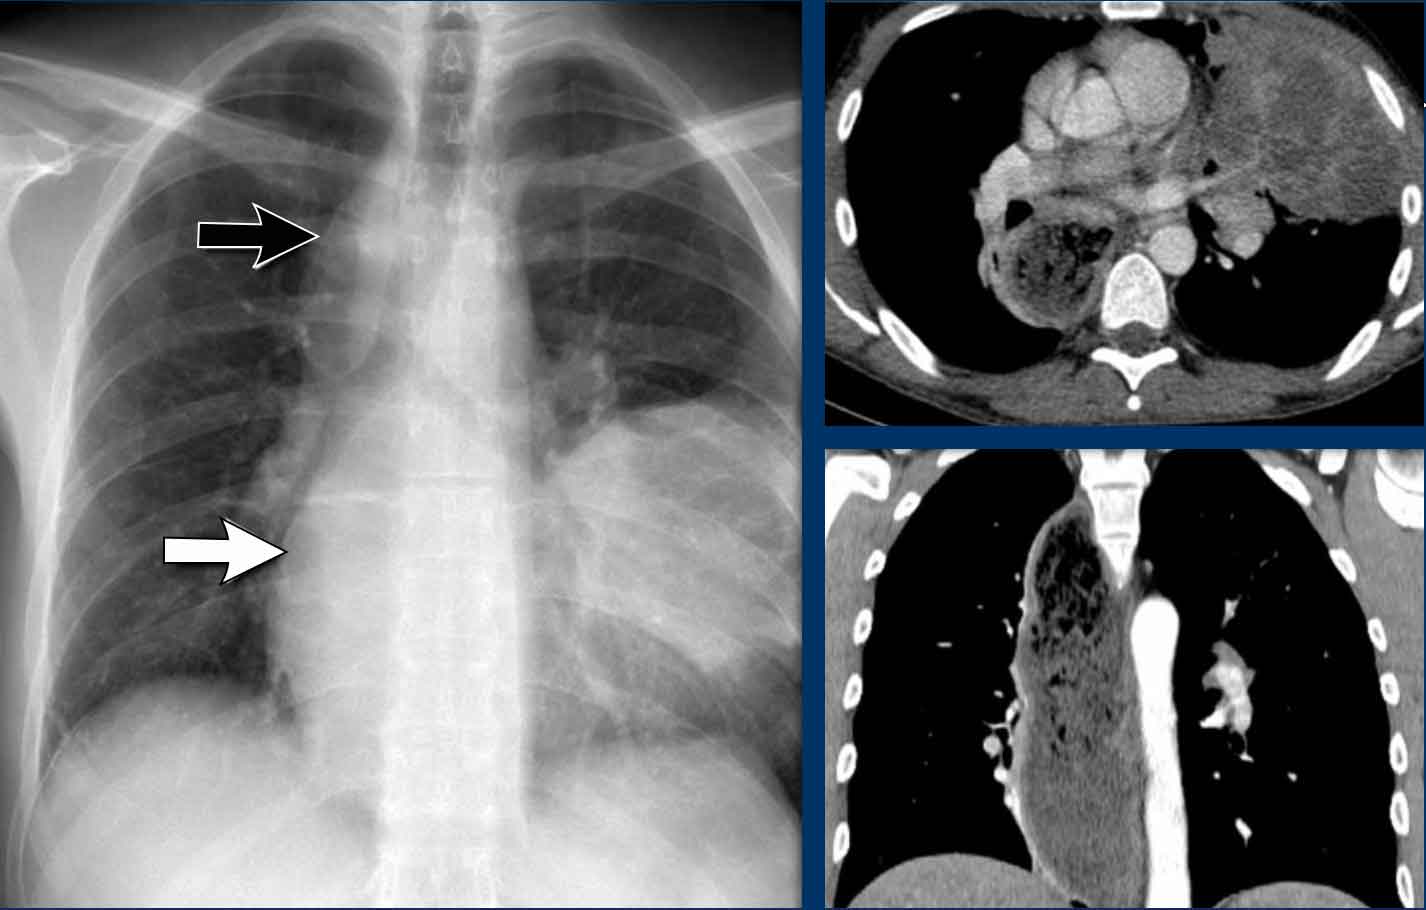

Displacement of the Azygoesophageal Line (2) – Subcarinal Lymphadenopathy

A common cause of displacement of the azygoesophageal line is subcarinal lymphadenopathy (station 7).

On the chest X-ray, note superior displacement of the azygoesophageal line just below the carina, consistent with enlarged subcarinal lymph nodes (black arrow).

Additional right paratracheal lymphadenopathy is seen, displacing the right paratracheal stripe (white arrow) and deviating the trachea to the left.

Continue with PET-CT...

PET Imaging

- PET-CT demonstrates extensive hypermetabolic lymphadenopathy in the mediastinum and neck, which is more conspicuous than on chest radiography.

- Cervical lymph nodes are involved—an important finding as they are accessible for biopsy.

Continue with images of CT and ultrasound...

CT Imaging

- Contrast-enhanced CT shows bulky subcarinal lymphadenopathy displacing the azygoesophageal recess and compressing the left atrium.

- Biopsy of a cervical node confirmed small cell lung carcinoma.